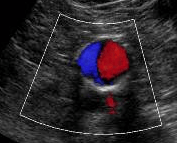

Ultrasound is done to detect aneurysms early, allowing for monitoring and treatment before they rupture. It is a painless, non-invasive test that locates the aneurysm, measures the dimensions and evaluates for plaque build up on the wall which may cause a narrowing.

Ultrasound is an effective and safe tool for the detection of aortic aneurysms and a highly accurate way to measure the size of an aneurysm with experience. Some aneurysms may pose difficulty in viewing due to their location, tortuosity features or calcific plaques limiting penetration of the soundwaves. We have many years of experience navigating these complications to provide your health care provider with accurate measurements and information. We provide your Doctor with extensive anatomical features and if the aneurysm is at a surgical size, further measurements to plan for your best treatment options.